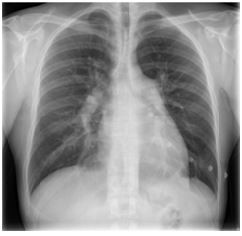

Homem, 42 anos, refere dispneia aos esforços há cinco meses, com sensação de opressão no tórax há uma semana. Nega tosse, expectoração ou chiado. Nega tabagismo. Exame físico: PS 120/79 mmHg; FC 86 bpm; saturação de O2 (ar ambiente) 91%. Ausculta cardíaca: hierfonese e desdobramento de segunda bulha em foco pulmonar. Turgência jugular bilateral. Pulmões limpo. Exames laboratoriais: hemoglobina 12,2 g/dL; leucocitos 8.500/mm³ plaquetas 152.000/mm³. Radiograma de toráx: